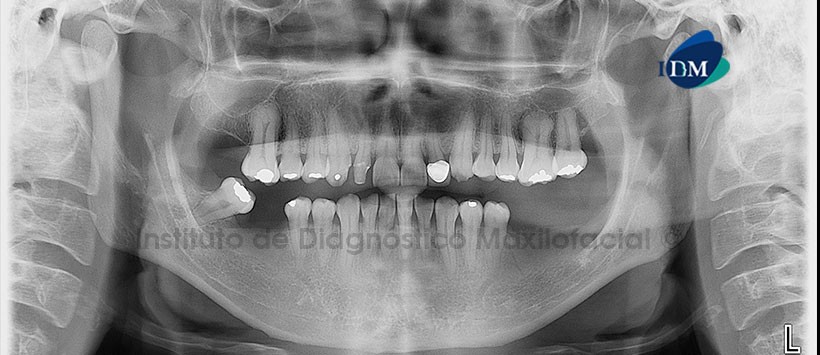

Paciente masculino, 33 años de edad, es referido al Instituto de Diagnóstico Maxilofacial (IDM) para evaluación tomográfica de zonas edéntulas con la finalidad de colocar implantes.

En la radiografía panorámica (Figura 1) se aprecia quiste de retención mucoso en seno maxilar derecho; Edéntulo parcial bimaxilar y múltiples restauraciones. Se puede evidenciar una alteración en la forma dentaria de las piezas 1.6 y 2.6 compatible con taurodontismo.